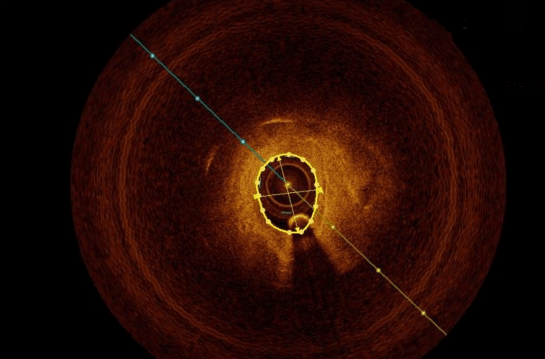

血管内光学相干断层成像(OCT)

- 斑块裂隙(纤维帽连续性)的判读

- 纤维帽厚度的测定

- 管腔狭窄程度的测定

- 钙化程度及模式(结节 vs 分散、浅表 vs 深在)的判读,以及钙化指数的测定

- 腔内血栓/斑块侵蚀的判读

- 新生血管/滋养血管的判读

- 介入治疗后靶血管的细节描述